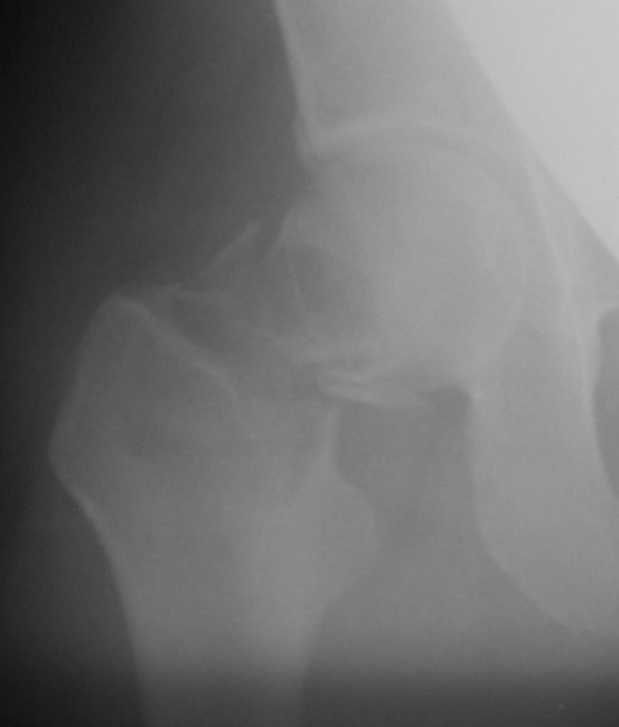

Приношу извинения, думал, что на прилагающейся рентгенограмме видно, что перелом произошел на месте обширной кисты, занимающей шейку и вертельную область. По характеру перелом многооскольчатый, дуга Адамса также представлена в виде осколков.

Если нет подозрений на первичную злокачественую опухоль, тогда опять остеосинтез, но конструкцией с угловой стабильностью, т.е. либо гамма/PFN (я бы выбрал), либо DHS. Без пластики. Вероятно, КТ могла

бы уточнить протяженность. Но головка выглядит хорошо, есть за что зацепиться.

"Поправил" рентгенограмму. Так не лучше?